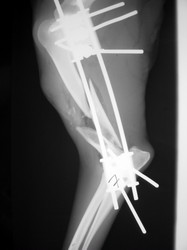

Fijación Externa

Fijación externa en IVOT

PRÁCTICAS CURSO DE FIJACIÓN EXTERNA PERFECCIONAMIENTO.

Húmero.